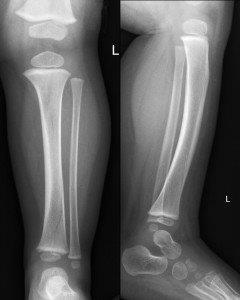

Fracture seen

Toddler fractures are not always apparent as in this X-ray